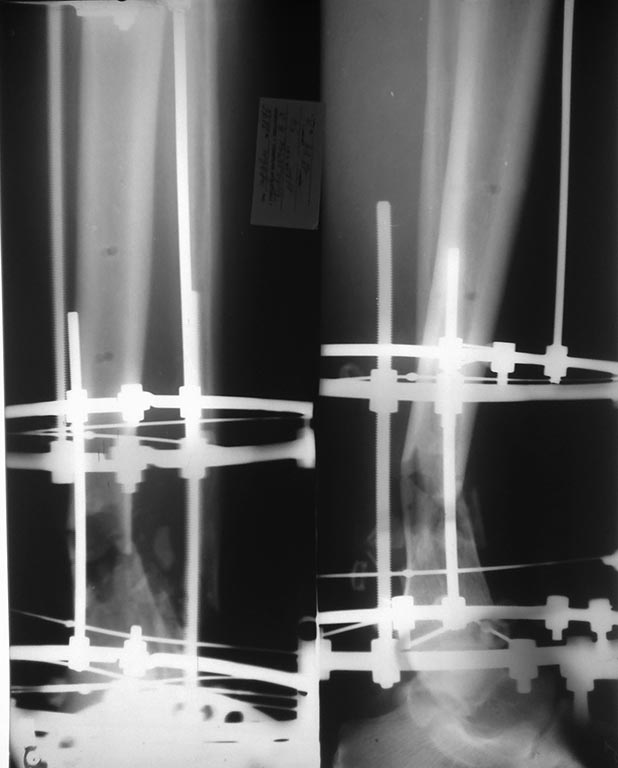

ПО дежурству ПХО раны (рана по внутренней поверхности голени в н/з), стабилизация отломков аппаратом внешней фиксации (стержневым). Через 4 дня у больного развился тяжелый алкогольный делирий, самостоятельно демонтировал аппарат!, после чего ходил на этой ноге по отделению. Через сутки после этого повторная операция - повторная обработка раны (которая уже увеличилась в размерах), удаление свободных костных фрагментов, стабилизация отломков аппаратом Илизарова. Из делирия вышел, компенсирован. Картина на данный момент на фотографиях - Р-графия и состояние раны. Кожные покровы по наружной поверхности также с участками некрозов. Температуры нет, анализы спокойные, из раны серозное отделяемое.

Возникает вопрос - что дальше? Как вариант планируется резекция пораженной большеберцовой кости (навскидку до 5 см), малоберцовой кости, постепенная компрессия в аппарате до сближения отломков, заживление раны. По сращению перелома, при адекватности пациента - решение вопроса об удлинении конечности.